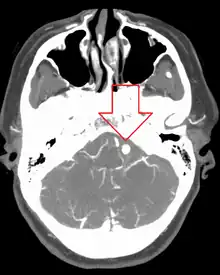

Diagnosis of a ruptured cerebral aneurysm is commonly made by finding signs of subarachnoid hemorrhage on a computed tomography (CT) scan. If the CT scan is negative but a ruptured aneurysm is still suspected based on clinical findings, a lumbar puncture can be performed to detect blood in the cerebrospinal fluid. Computed tomography angiography (CTA) is an alternative to traditional angiography and can be performed without the need for arterial catheterization. This test combines a regular CT scan with a contrast dye injected into a vein. Once the dye is injected into a vein, it travels to the cerebral arteries, and images are created using a CT scan. These images show exactly how blood flows into the brain arteries.[38]